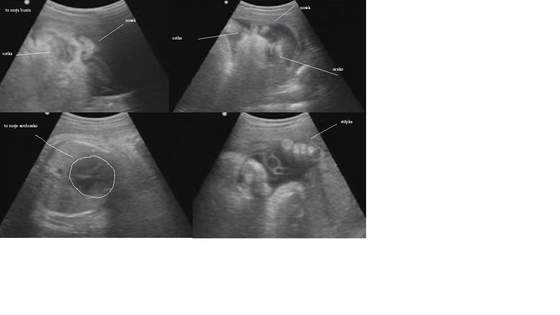

Na zdjęciach- ja i mój mąż Ariel oraz nasza dzidzia w ostatnim USG :-)